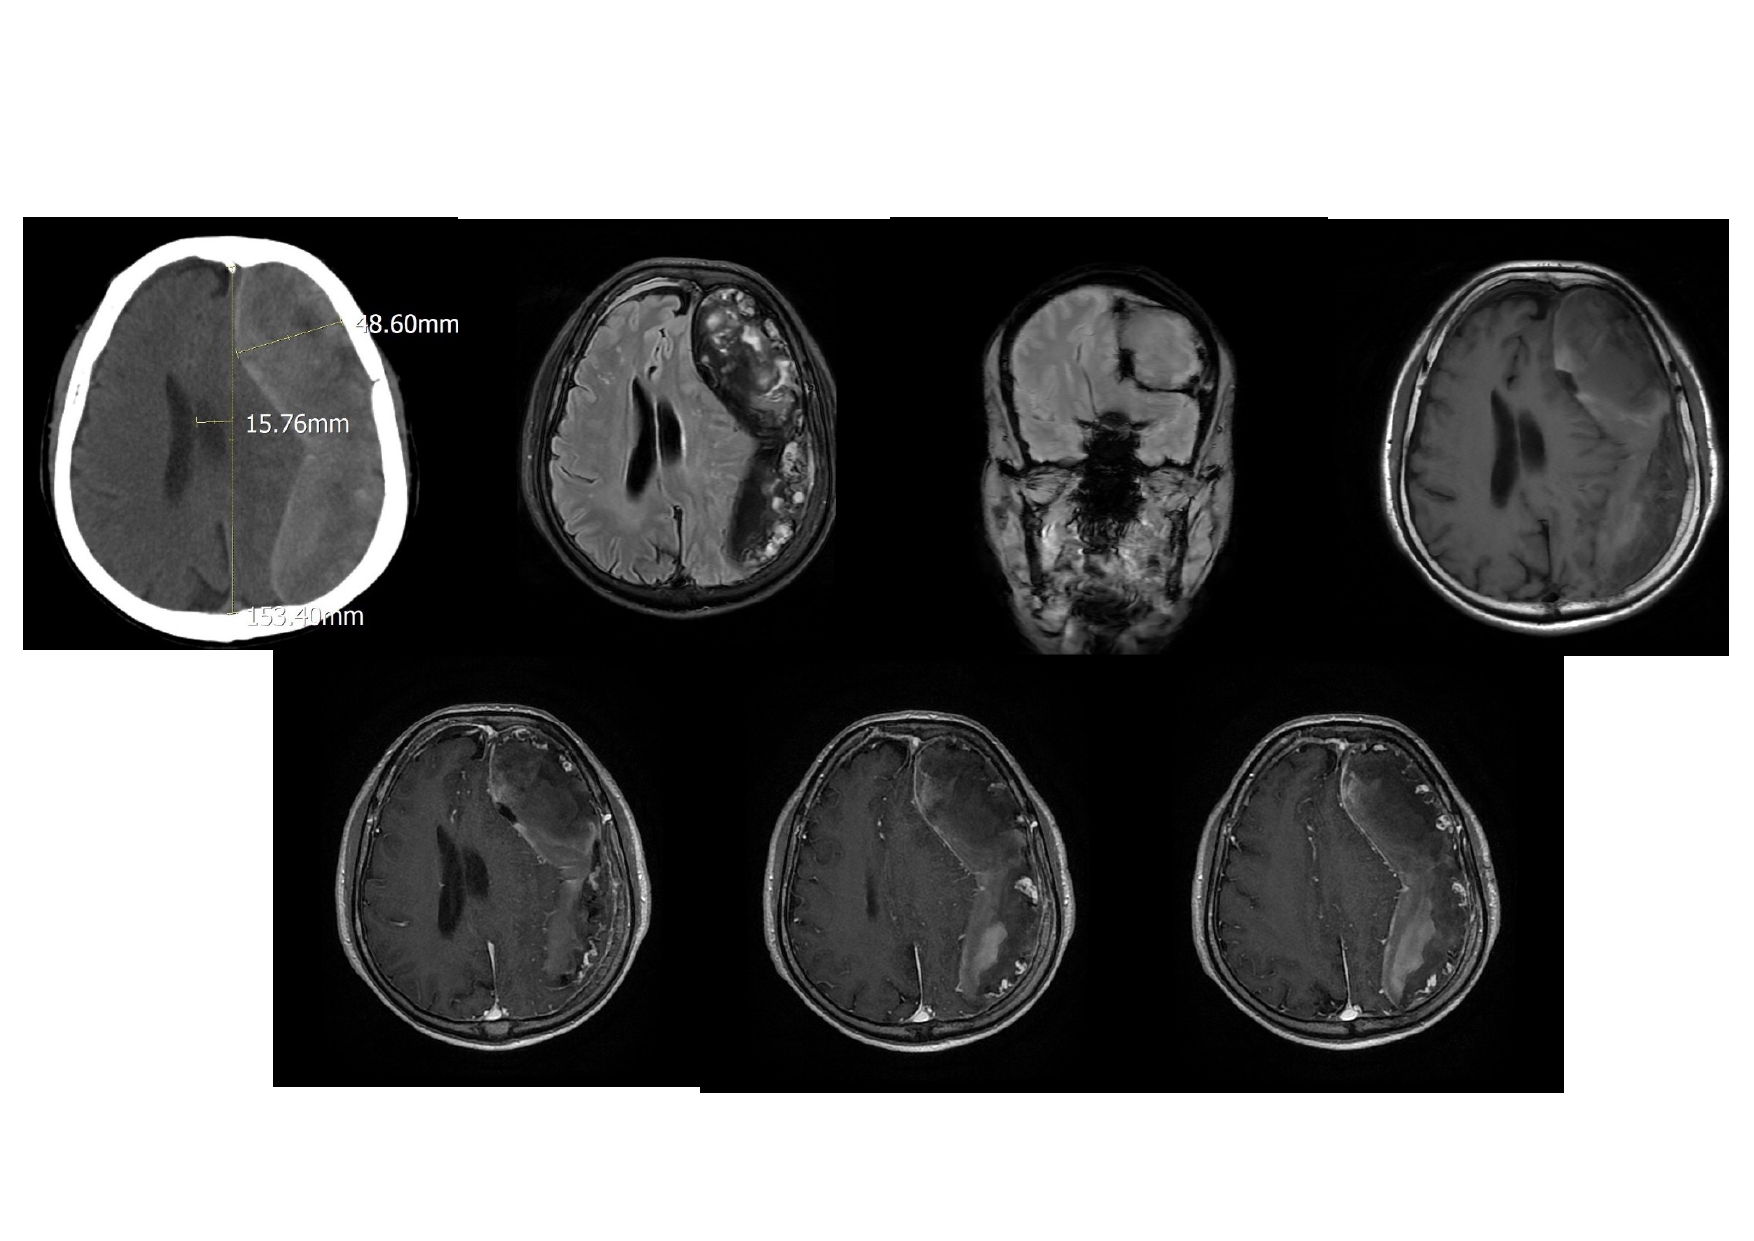

| 13:30 - 14:10 | Surgical management of skull base trauma Endovascular Management of Post-Traumatic Intracranial Vascular Lesions | Assoc. Prof. Nguyen Trong Yen Dr. Nguyen Ngoc Cuong | |

| 14:10 - 15:10 | DEBATE 2 | Recurrent chronic subdural hematoma– surgical or endovascular intervention? Surgical: Assoc. Prof. Duong Dai Ha Endovascular: Assoc. Prof. Le Thanh Dung | Moderator: Prof. Christian Matula Assoc. Prof. Duong Dai Ha | |

| 15:10 - 16:10 | Interactive Case Demonstration and Discussion II: ~20 minutes each, (5 minutes presentation followed by 15 minutes discussion) Practicals: How I am doing it? Participants present case presentations about how they do it? The faculty comment on and discussion. 1. Endoscopic approach in post-traumatic CSF leakage - Dr. Nguyen Thanh Xuan 2. Endovascular approach in CCF - Assoc. Prof. Le Thanh Dung | Prof. Christian Matula International & local faculties Participants | |